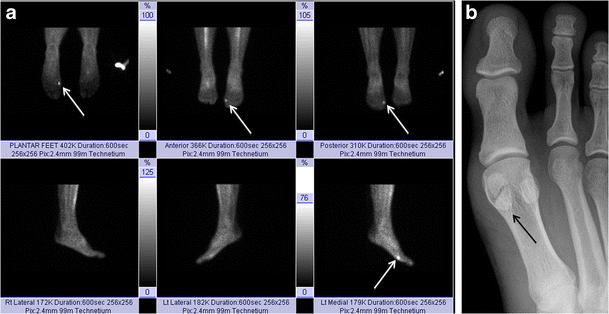

Sesamoiditis. Bone scan of the bilateral feet (a) in a patient with plantar foot pain reveals nonspecific but intense tracer uptake localising to the medial hallucal sesamoid. AP radiograph at the first toe (b) reveals a bipartite medial hallucal sesamoid with no diastasis, fragmentation or sclerosis. The patient was diagnosed with bony sesamoiditis

Osteoarthritis. Bone scan of the bilateral feet (a) shows nonspecific but intense tracer uptake localising to the medial hallucal sesamoid (arrows). Lateral radiograph at the first toe (b) reveals joint space narrowing and osteophyte formation at the medial sesamoid-metatarsal articulation (arrow), consistent with osteoarthritis